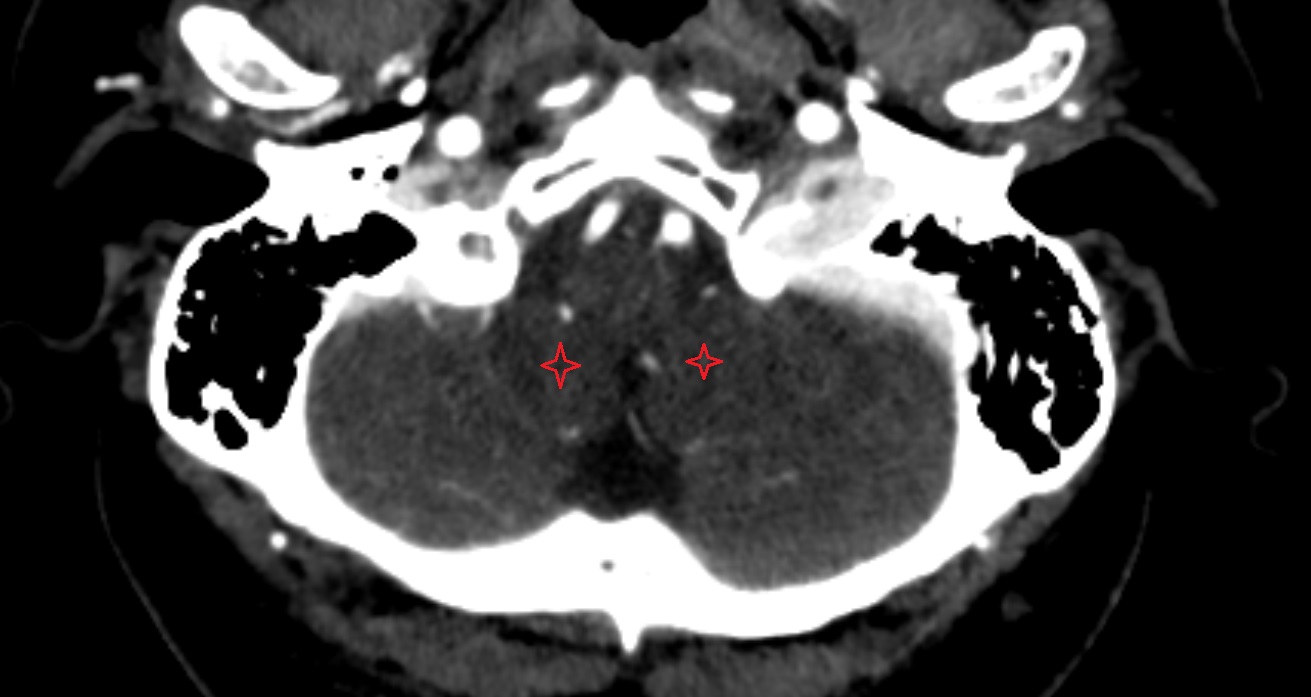

- Cerebellum